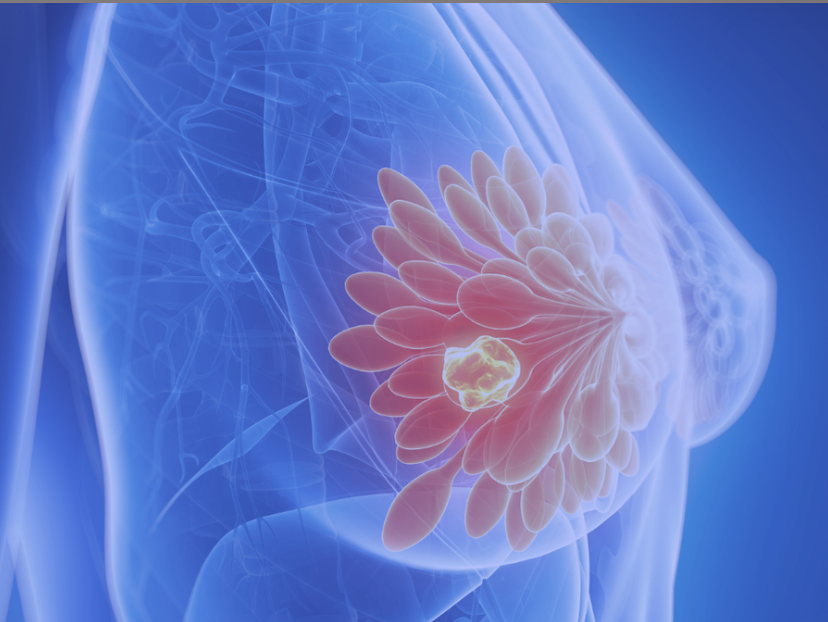

Deeply understand the health of your breast tissue

1-3pm Lymphatic Breast Health

The best way to conduct self-examinations that Western doctors don't teach